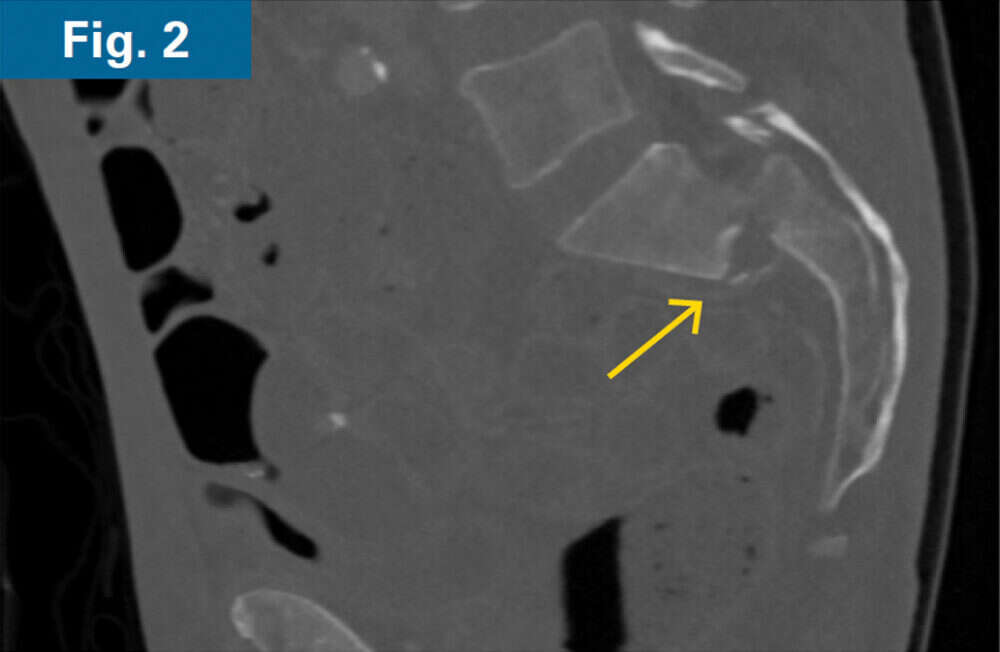

• 62 y/o male with COPD and 1 month old sacral U-type fracture after motorcycle crash (Figs. 1 and 2)

• Comminution and displacement of the right side component of his sacral U-type fracture significantly decreased the osseous corridor for placement of trans-sacral style screw in S1 requiring an iFuse TORQ® implant to provide sufficient fixation

His pelvic abscesses were debrided and washed (lateral window) and antibiotic beads were placed followed by percutaneous placement of bilateral ilio-sacral style S1 implants. Intraoperative CT scan was performed after placement of 3.2 mm guidewires to confirm safe path of placement for iFuse TORQ implants in the setting of poor visualization of the foramen (Fig. 3). Bilateral 13.5mm iFuse TORQ implants were placed and the patient was allowed weightbearing as tolerated for activities of daily living at his home (Fig. 4).